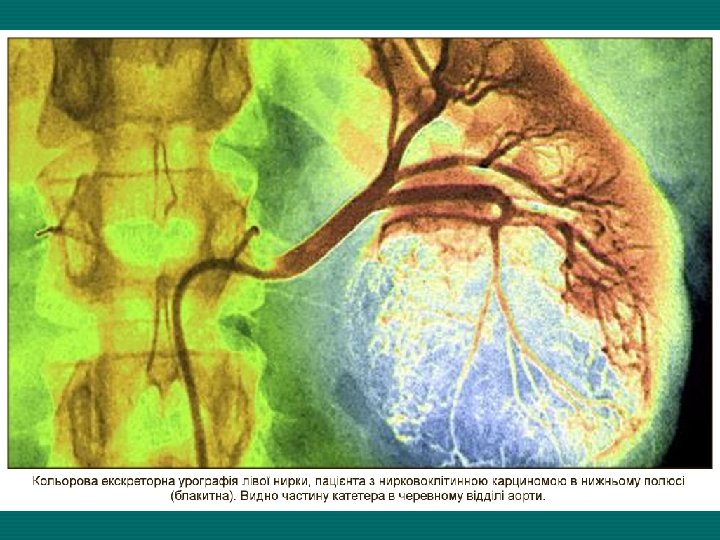

Диагностика МЕТОДЫ ДИАГНОСТИКИ РАКА ПОЧКИ ЛАБОРАТОРНЫЕ • Определение уровня гемоглобина (обычно более низкий за счет гематурии) • Определение уровня ШОЕ (обычно высокое); • Определение уровня креатинина и мочевины (функциональное состояние почек), щелочной фосфатазы (метастазы в печень, кости); • Определение показателя уровней онкомаркеров Tu M 2 - PK, SCC, CA 125 ИНСТРУМЕНТАЛЬНЫЕ • Рентгенологические исследования: - обзорная рентгенография - екскреторная урография - ретроградная пиелография - КТ ОБП (с контрастированием) - ренография. • УЗИ почек; • Тонкоигловая пункционная биопсия под контролем УЗИ; • Сцинтиграфия почек из 99 m. Тс-ДМСА; • Вазография НПВ и аорты (исключение тромба).

Справа предоставлено вниманию компьютерные томограммы с визуализацией опухолей левой почки